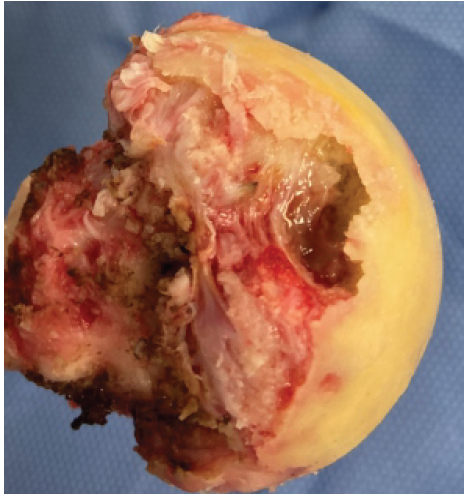

The femoral head was found to be partially destroyed (Fig. 4), and the acetabulum was devoid of any cartilage.

Figure 4: Destruction of the femoral head by infection and osteonecrosis with associated synovitis.

Significant synovitis and granulation tissue noted during surgery were meticulously debrided. Tissues were sent for aerobic and anaerobic culture, mycobacterium, fungus, and histopathology (Table 3).